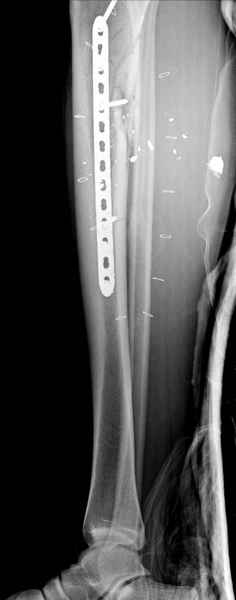

Здесь несколько примеров из нашей практики:

1 неполный перелом большеберцовой кости перкутанная пластина